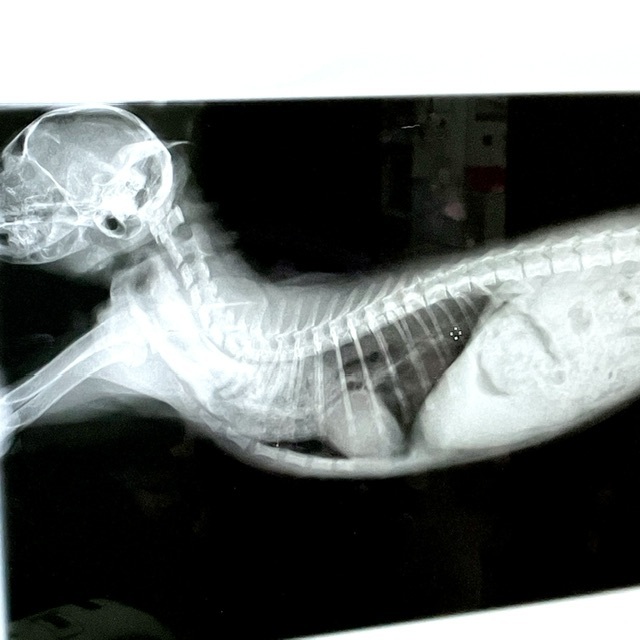

助けてください。難病【特発性乳び胸】に立ち向かう1歳の豆柴のまめ太

- 支援総額

- 600,000円

- 支援者

- 104人

- 終了日

- 7/5